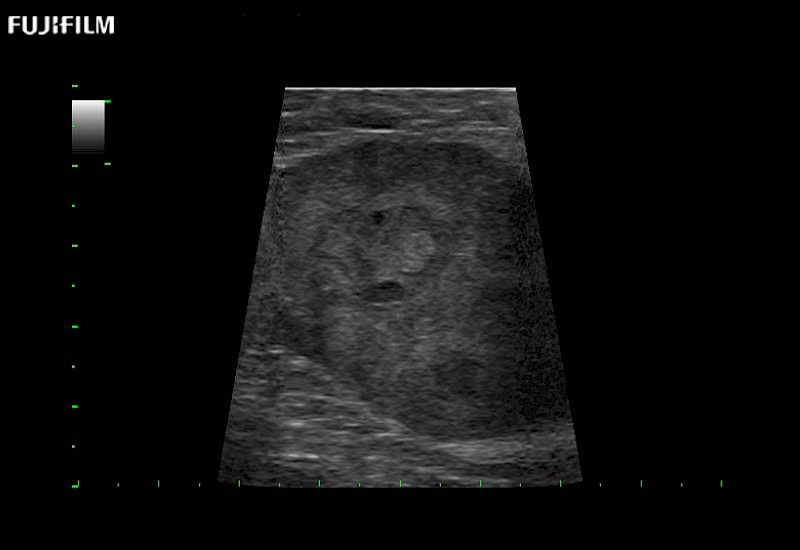

Exclusive linear array robotic surgery transducer.

Features:

Main Specifications: